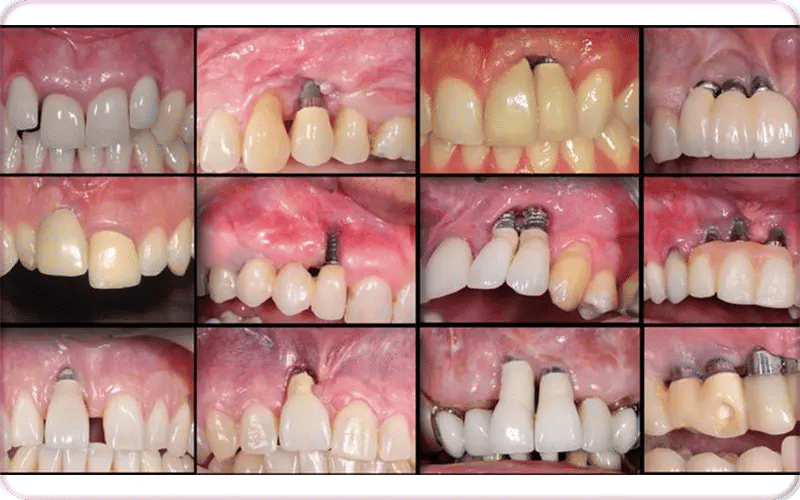

Before and After Bone Loss Bad Dental Implants Pictures

5. Visible issues in scans or images (bad dental implants xray / bad dental implants pictures): X-rays or clinical photos may reveal bone loss, poor placement, or structural failure not visible to the naked eye.